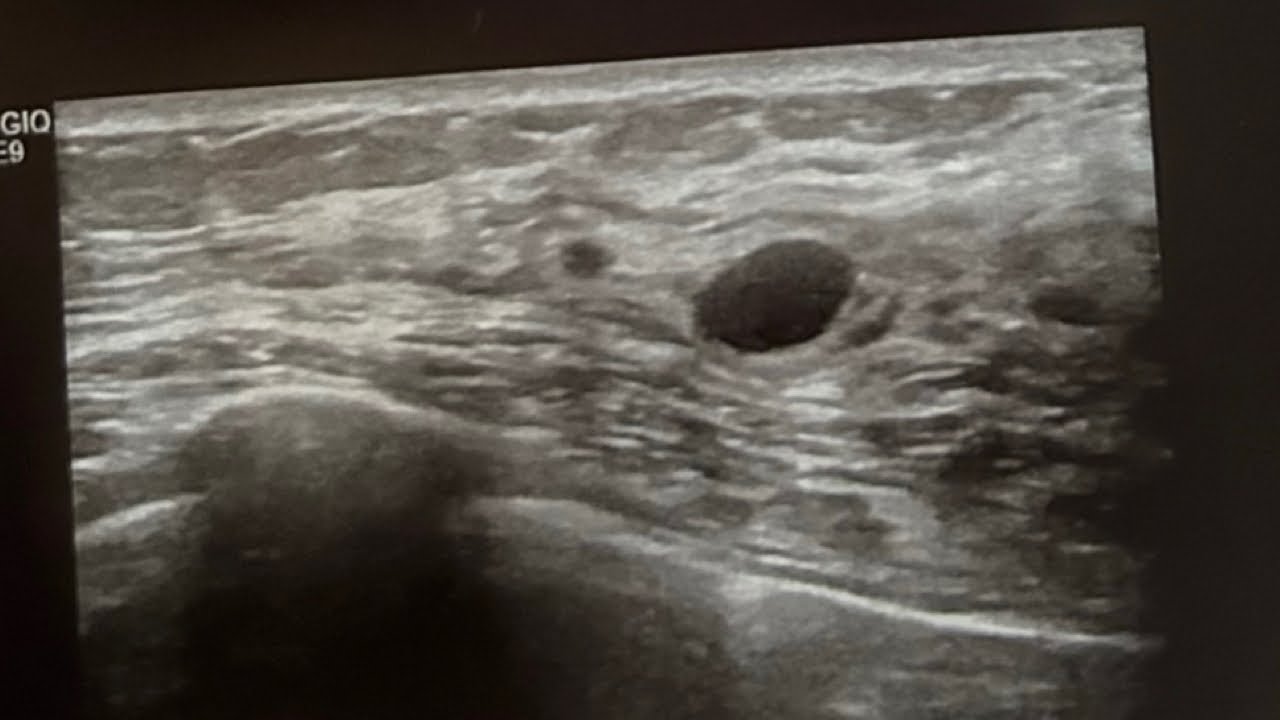

Ultrasound Guided Cyst Aspiration and Minimally Invasive Breast Biopsy

Ultrasound Guided Cyst Aspiration and Minimally Invasive Breast Biopsy Painful Breast Lump Biopsy a breast biopsy is a simple procedure in which a doctor removes a small sample of tissue from a lump in the breast to send to a laboratory for testing. Taking painkillers and wearing a. Healthcare providers usually use a local anesthetic or general anesthetic for. It’s one of several tests. The kind recommended for you will be determined. Painful Breast Lump Biopsy.